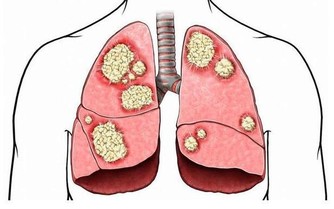

一、腹痛

首先要和大家說的就是,腹痛。這是一種被很多人所忽略的疾病。因為有些人會覺得出現這種情況,只是因為自己吃錯了食物,又或者是冷的東西吃多了,從而刺激腸胃所造成的。並且很多人出現這種情況的時候,身體都能夠自動的分解,比如說,就疼那麼一會兒之後就不痛了。

但是在出現這種情況的時候,就需要你敲響健康的警鐘了。那就是你持續一周到兩周的時間之內,下腹總會有疼痛感,又或者是有下墜感的時候,你就需要非常的小心,因為這有可能是大腸癌的前兆。

而且在你持續性的腹痛時,平常的排便也出現了變化,比如說排便次數明顯的增多,並且有時還會出現血便,並且還會出現便秘。再加上平時體重莫名的開始降低,那麼在這個時候你就需要趕緊去醫院檢查。

很多人由於不明白情況,往往會認為上文中所出現的這種情況,是由於痔瘡又或者是腸炎引起的,從而不去醫院做檢查。

時間一長,就會錯過了最佳的治療時間,從而造成無法挽救的後果。所以大家在平時要是總會腹痛,並且出現上文中所說的這些癥狀的時候,一定要儘早的去做檢查。